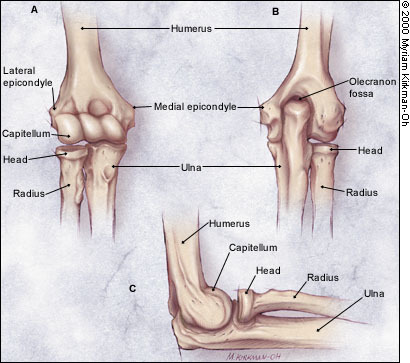

Remind yourself of the boy anatomy of the elbow